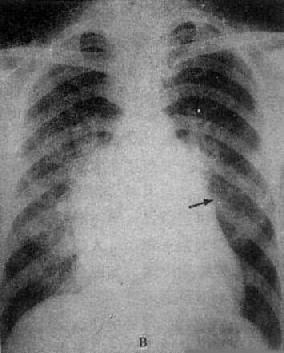

单纯二尖瓣狭窄X线表现(图3-2-15)为:①心脏增大,左心房和右心房增大,左心耳常明显增大;②主动脉球缩小,主要原因是左心室血液排出量减少,主动脉发育障碍或心和大血管向左旋转时,主动脉弓折叠;③左心室缩小,心尖位置上移,心左缘下段较平直;④二尖瓣瓣膜钙化,系直接征象;⑤肺瘀血和间质性水肿。上肺静脉扩张,下肺静脉变细。有时还可见肺野内出现直径1~2mm大小的颗粒状影,为含铁血黄素沉着。

图3-2-15 二尖瓣狭窄

A.右前斜位:右心室增大,肺动脉段突出(↑),心前间隙变窄(↑),左心房轻度增大;B.后前位:心增大,呈二尖瓣型,右心室增大,肺动脉段突出,左心耳增大,出现第三弓(↓),有肺瘀血表现;C.左前斜位:右心室增大,左心房增大不明显;左心室不增大。